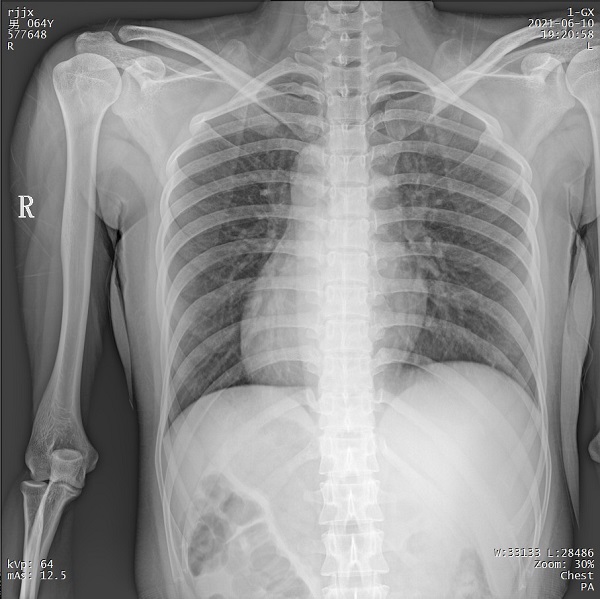

二、1ms 短時曝光 定格心肺運動瞬間影像

PLX5500系列移動DR能夠在1ms的曝光時間內(nèi)輸出足量的X射線,獲取清晰圖像。特別適用于拍攝肺炎、塵肺病、肺結(jié)核等難以憋氣的患者,避免了因患者肺部呼吸運動而產(chǎn)生的運動偽影的影響,瞬間定格清晰圖像,以供醫(yī)生準(zhǔn)確診斷。